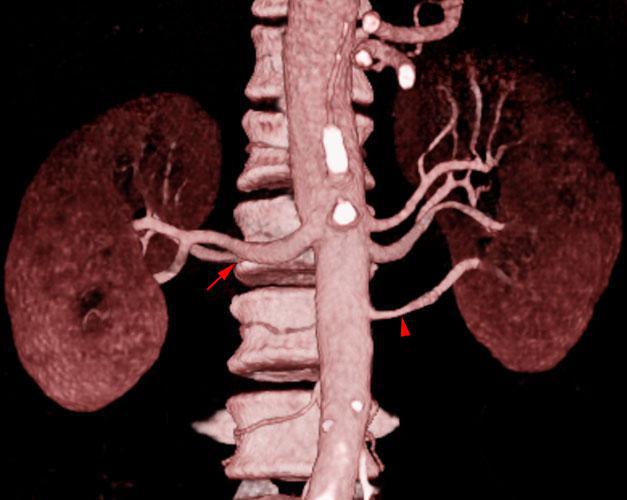

Arterias renales polares